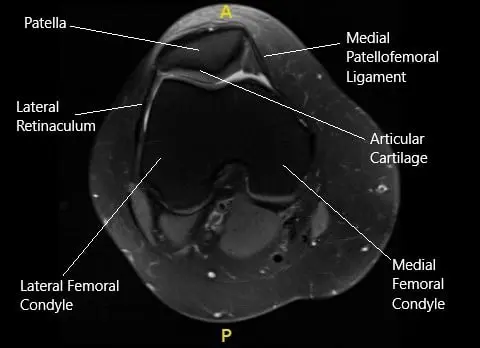

MRI of the right knee in axial section.

The MRI of the right knee suggested patellar mal-tracking. Due to the failure of the conservative management, the patient was advised surgical management. The risks, benefits, and potential complications were all discussed at length with the patient. The patient agreed to go ahead with the procedure.